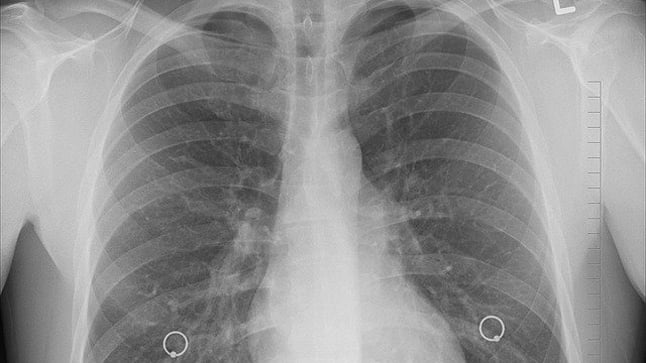

El diagnóstico de neumotórax se sospecha con los síntomas que refiere el paciente y con la auscultación del pulmón y se confirma al realizar una radiografía del tórax donde se observa que no hay tejido pulmonar en una zona del tórax. A veces es necesario realizar una gasometría para determinar la cantidad de oxígeno en sangre y más raramente, un TAC si se va a proceder a una intervención quirúrgica.